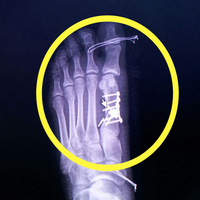

Yalova'da ayağındaki rahatsızlık nedeniyle devlet hastanesine müracaat eden Büşra Nergiz, kırık ayak parmağı yerine sağlam parmağını ameliyat edip 5 platin taktığını ileri sürdüğü doktor hakkında savcılığa suç duyurusunda bulunmuş, hastane yönetimi doktor hakkında idari soruşturma başlatmıştı.